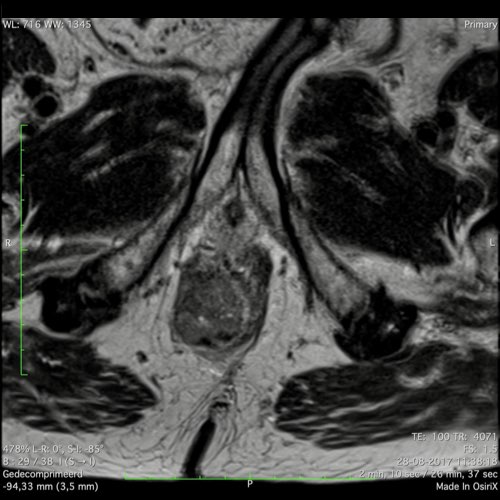

Hình ảnh

Các hình ảnh được cung cấp cho thấy ung thư biểu mô tế bào nhẫn với tình trạng dày lan tỏa thành trực tràng, hình ảnh bia bắn điển hình, và sự xâm lấn mỡ mạc treo trực tràng.